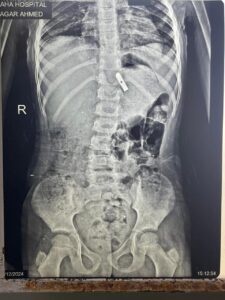

أوضح البيان أنه على الفور جرى حجز الحالة بالمستشفى، وجرى عمل اللازم من إشاعات وتحاليل وجرى تشخيص الحالة بوجود جسم غريب داخل المعدة وعلى الفور جرى دخول الطفلة إلى غرفة العمليات.

وجرى استخراج قطعة معدنية حادة من برايه القلم الرصاص من جدار المعدة باستخدام منظار الجهاز الهضمي وقام الأهل بتوجيه كل الشكر والعرفان للفريق الطبي وكل من تعاون في إنقاذ حياة طفلتهم.